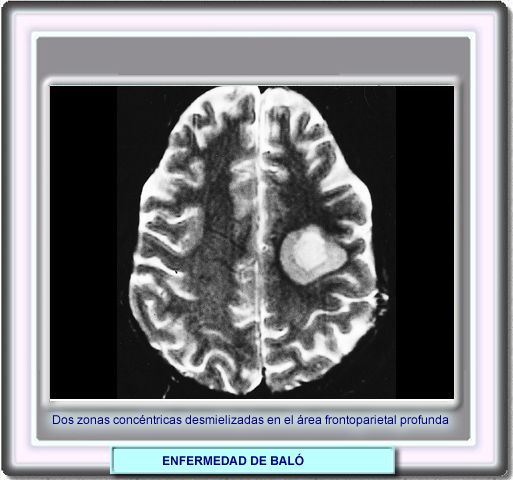

La resonancia magnética en T2 muestra a veces las áreas separadas

de desmielinización en la materia blanca profunda representada por

dos grados diferentes de la señal en T2